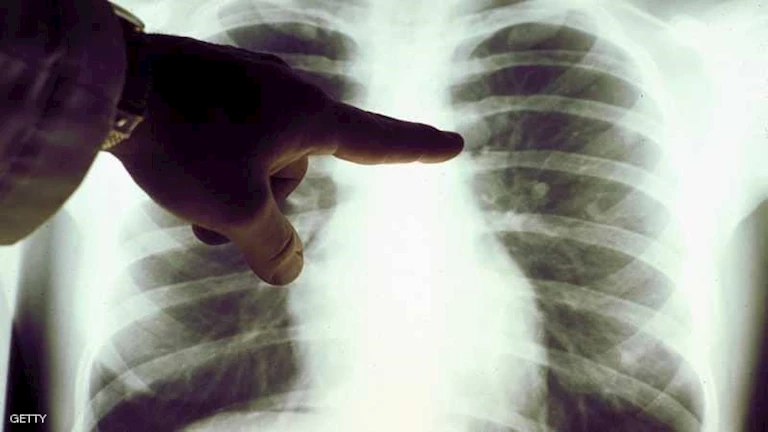

يُعد سرطان الرئة السرطان الأكثر انتشاراً عالمياً والسبب الرئيسي للوفيات المرتبطة بالسرطان. ويعقد اء آمالهم الآن على أن يتمكنوا من منع ظهور أنواع معينة من السرطان بشكل أساسي.